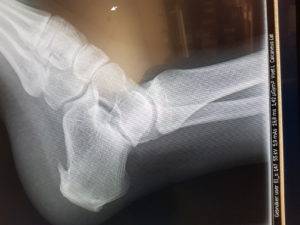

Gelukkig kan ik gelijk bij de huisarts op het eiland terecht, hij begrijpt mn zorgen en twijfelt of het allemaal nog heel is. Hij maakt foto’s…tja..wel hielspoor, nu zo te zien niets gebroken, dat is soms later pas te zien en de radioloog kijkt ook nog even mee morgen.als ik niet gebeld wordt kan ik gaan lopen.

Dat haakje onder de hak is de hielspoor, de boosdoener in ieder geval. Ik krijg 2 soorten pijnstillers mee en het advies om de hiel te laten tapen. Dankzij mn zus die een goede therapeut kent, word ik supersnel en goed geholpen. Ik ben echt heel dankbaar en besluit maandag om de volgende dag wél naar Porto te gaan. Op hoop van zegen en de plannen al bijstellen voordat ik ben begonnen. De eerste les al geleerd: ‘rustig aan doen, niets forceren, tis geen wedstrijd, opbouwen, het gaat om de reis en niet om de aankomst’. De eerste Camino cadeautjes ontvangen. Bedankt Piet Jan, Jeroen Jeanette en Henry. En mocht het niet gaan dan is het niet anders.